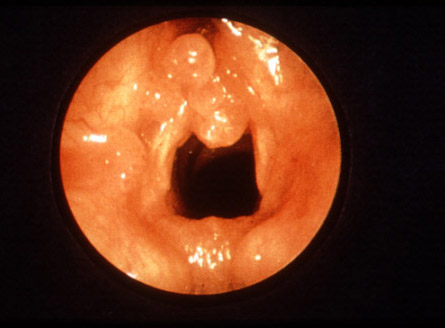

Endoscopic view illustrating laryngeal respiratory papillomatosis.